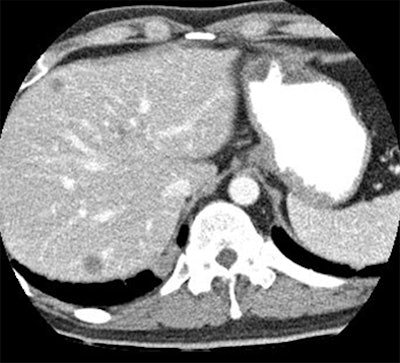

| Hypovascular liver lesions at DSCT are more conspicuous at 80 kVp (top) than at weighted-average data simulating 120 kVp. Images courtesy of Dr. Michael Macari. |

The mean size of the metastases was 2.6 cm. The mean standard deviation of the attenuation difference between the metastases and the normal liver at 80 kVp was 72.3 ± 27 HU at 80 kVp versus 54.2 ± 18.7 at 120 kVp. The mean attenuation difference was significantly higher at 80 kVp (p < 0.001). In two cases, metastases were detected only at 80 kVp.

"We also noted that the attenuation of the normal liver was greater at 80 kVp [132.1 ± 19.6 HU] than at 120 kVp [100 ± 14.3 HU], and it's this difference in the attenuation of the normal liver that really tells you the difference between normal liver and the metastasis," Macari said.

The contrast-to-noise ratio was greater at 80 kVp even though these are noisier images, because the contrast is so much greater.